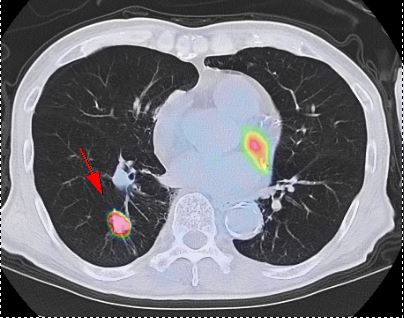

⑥CTやMRIなどと組み合わせるとより詳しくがんがわかります

CTやMRI検査は、体の中の組織や細胞の「かたち」を画像でとらえ、周囲臓器との関係をみることによってその異常を見つけます。これに対しPET検査は、細胞の「活動状態」を画像でとらえる検査法です。

PET検査を組み合わせることで、違った種類の情報が加わり、CTやMRIなどの検査だけでは見つかりにくかったがんが、発見しやすくなります。

またPETはCTやMRIに比較して空間分解能が低く異常が発見されても病気がどこにあるかはっきりわからない場合があります。そこでCTやMRIなどと合成(フュージョン)すると、病変部位の解剖学的な「形や大きさ」を正確に把握することができます。

▲早期右乳癌